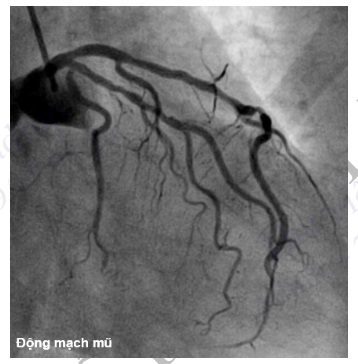

Hình 4.93. Chụp ĐMV trái ở tư thế nghiêng phải chếch chân đánh giá ĐM mũ và đoạn gần ĐM liên thất trước